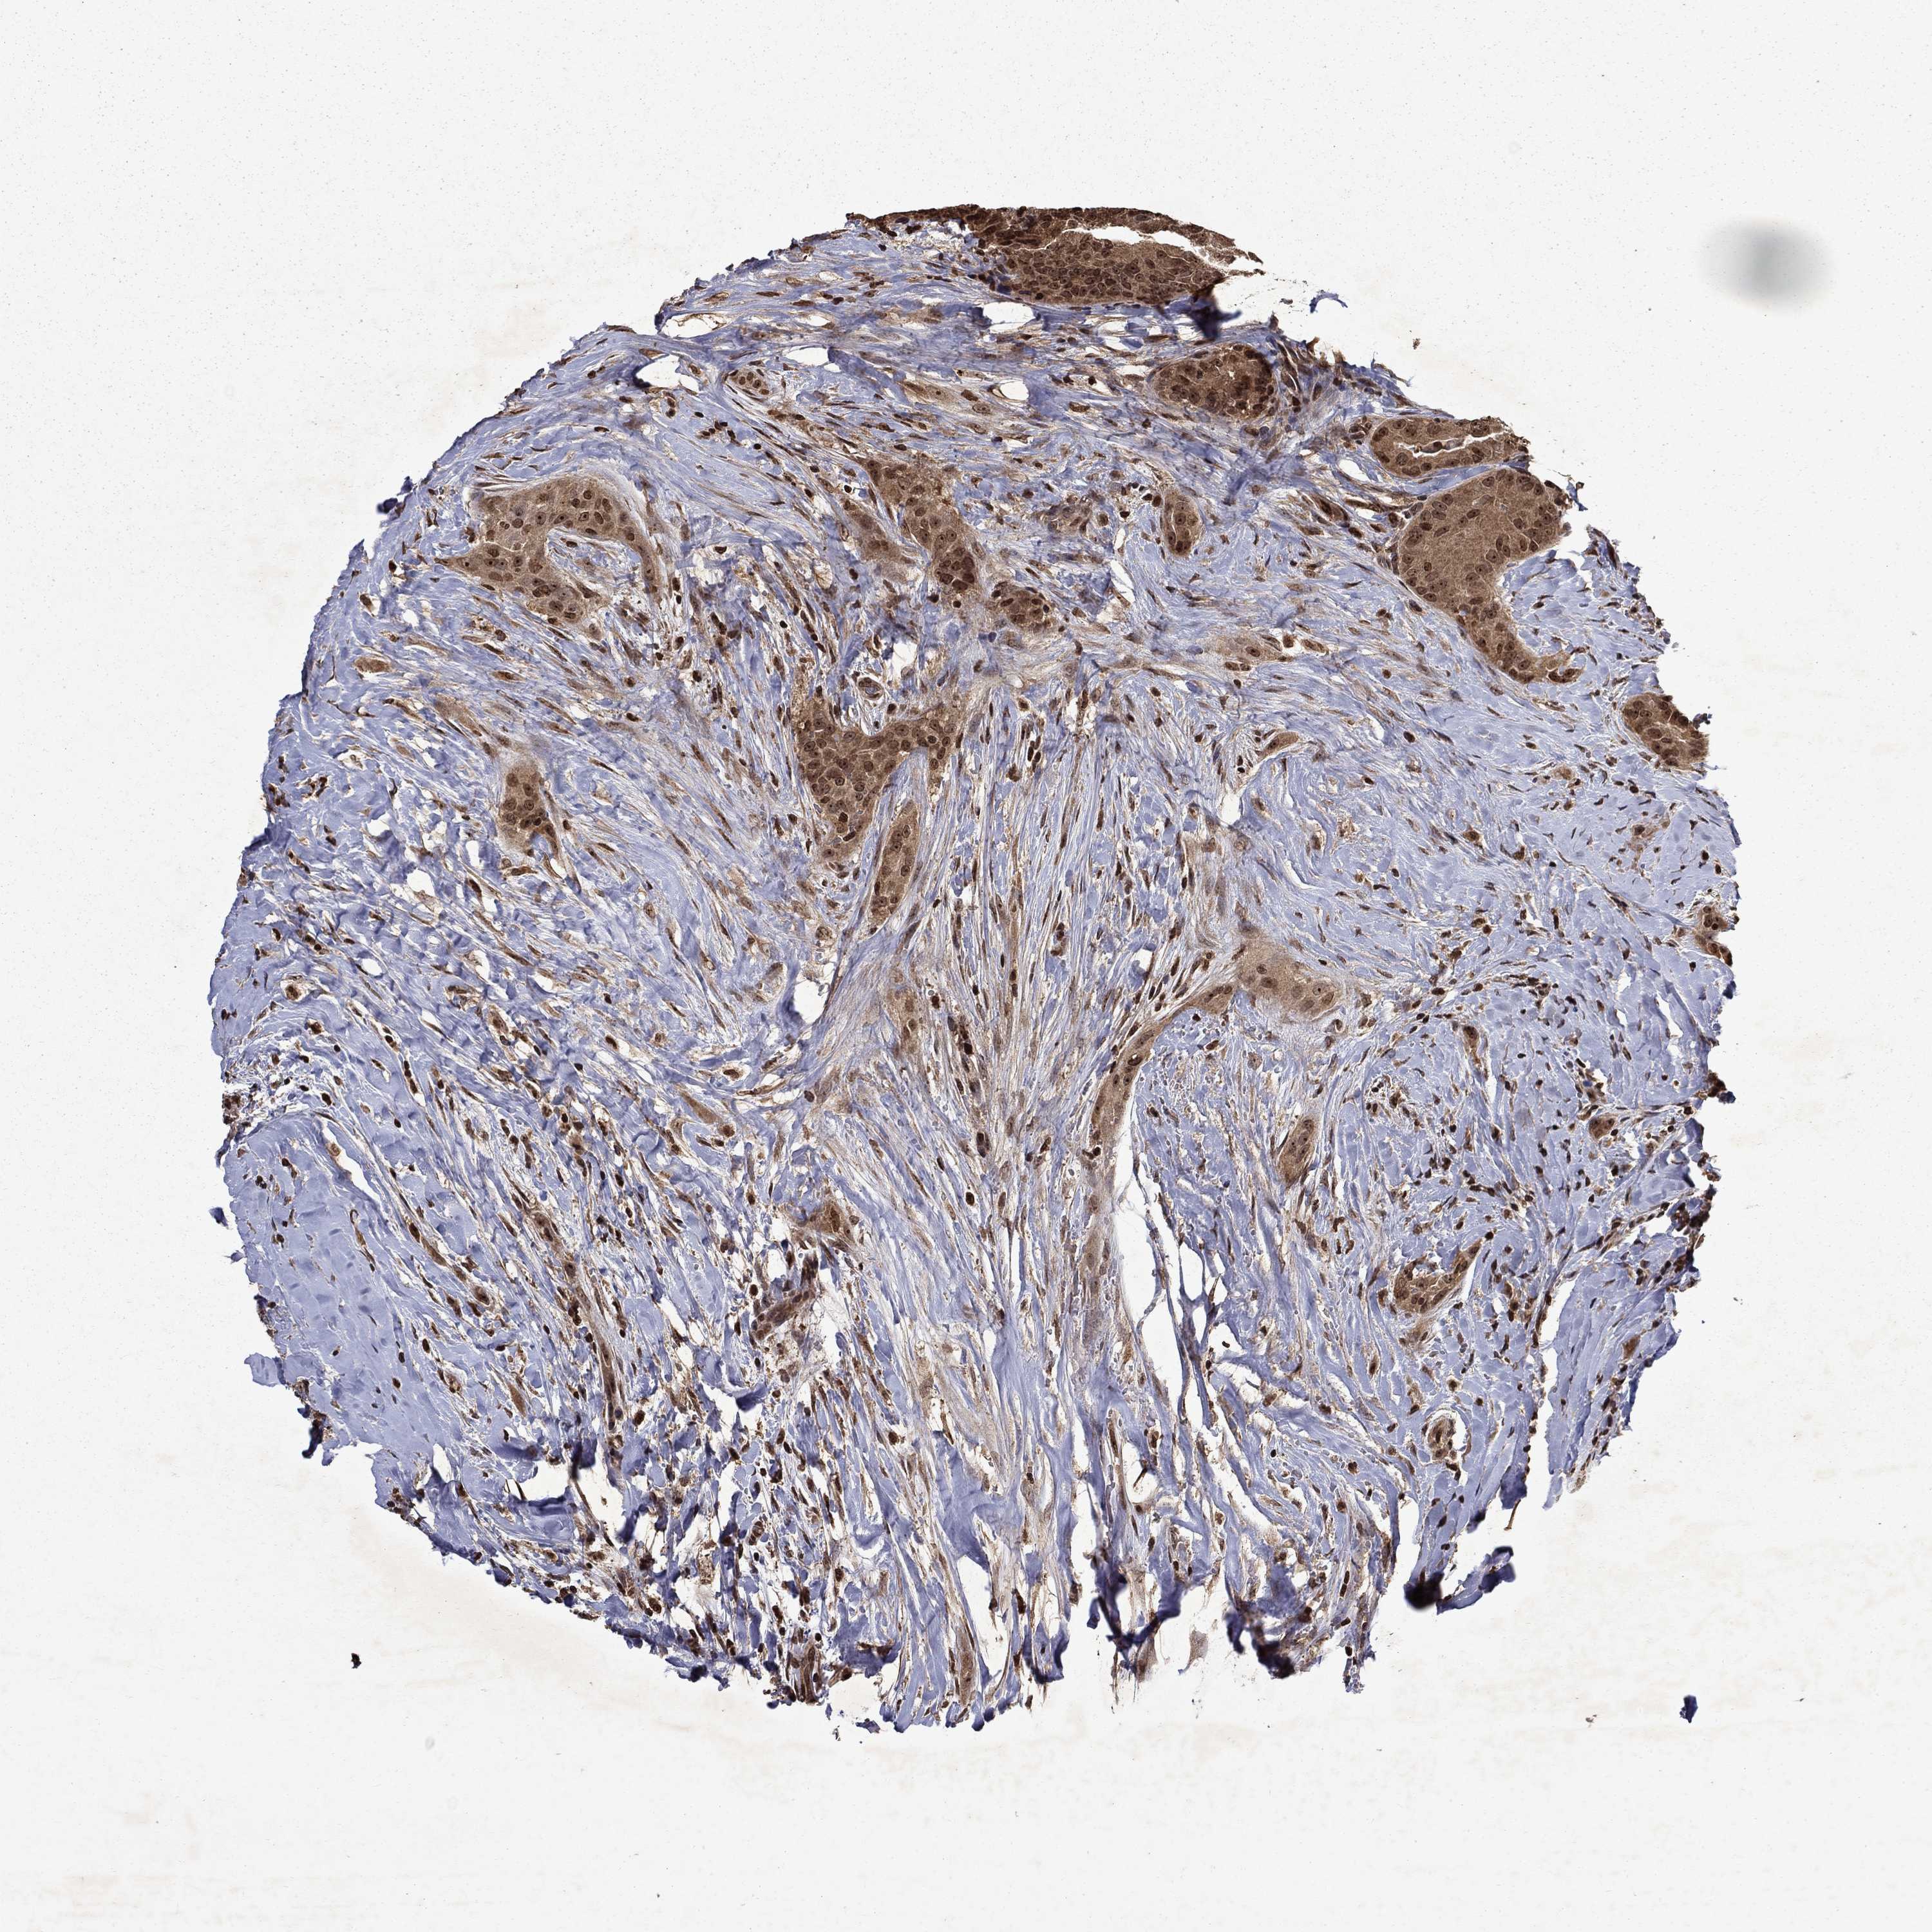

THYROID CANCER - Protein expressioni

A mouse-over function shows sample information and annotation data. Click on an image to view it in a full screen mode. Samples can be filtered based on level of antibody staining by selecting one or several of the following categories: high, medium, low and not detected. The assay and annotation is described here.

Note that samples used for immunohistochemistry by the Human Protein Atlas do not correspond to samples in the TCGA dataset.

Antibody stainingi

Antibody staining in the annotated cell types in the current human tissue is reported as not detected, low, medium, or high, based on conventional immunohistochemistry profiling in selected tissues. This score is based on the combination of the staining intensity and fraction of stained cells.

Each image is clickable and will lead to virtual microscopy that enables deeper exploration of all samples and also displays staining intensity scores, fraction scores and subcellular localization as well as patient and tissue information for each sample.

Antibody HPA054483

Antibody HPA064504

Staining

High

Medium

Low

Not detected

Intensity

Strong

Moderate

Weak

Negative

Quantity

>75%

75%-25%

<25%

None

Location

Nuclear

Cytoplasmic/membranous

Cytoplasmic/membranous,nuclear

Papillary adenocarcinoma, NOS

Follicular adenoma carcinoma, NOS